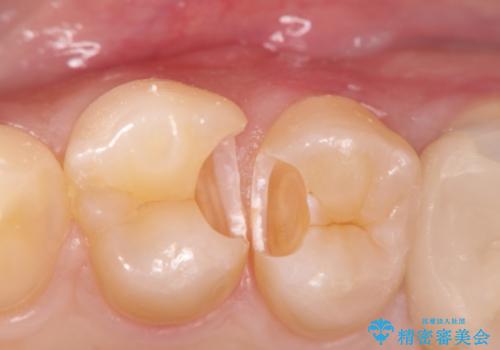

- 晩期残存した下顎乳中切歯の変色を主訴に来院されました。

後続永久歯は先天性欠如しており、下顎前歯のブリッジにて補綴治療を行なっております。